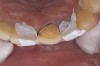

Figure 9: Tooth No. 9 minimally prepared for resin layering on the labial surface.

Figure 9

Figure 10  Tooth No. 9 with no preparation on the palatal surface to restore lost form with bonding resin.

Figure 10

During the next appointment, a palatal index of the approved provisional was fabricated with putty silicone. This enabled the clinician to precisely build the lingual surfaces and incisal edges of teeth Nos. 6 through 11. The provisional mock-up resin on No. 9 was removed, and the underlying labial tooth was roughened with an abrasive diamond bur. No tooth structure was removed from the palatal surface, and unsupported enamel was rounded off from the labial. An ultrathin dry cord was placed in the gingival sulcus on No. 9 (Figure 9 and Figure 10). Teflon tape was used to isolate No. 9 from adjacent teeth. Then 37% phosphoric acid was used to totally etch the labial surface for 10 seconds and the palatal surfaces on No. 9 for 5 seconds. Single bond was applied and spread uniformly across the tooth and light-cured for 20 seconds.